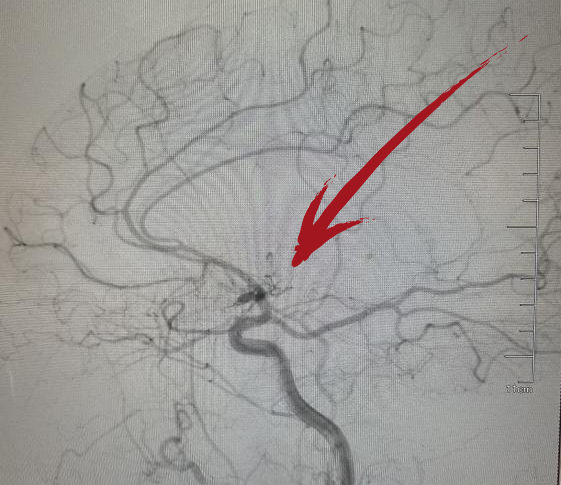

▲术前DSA右侧大脑中动脉起始段闭塞